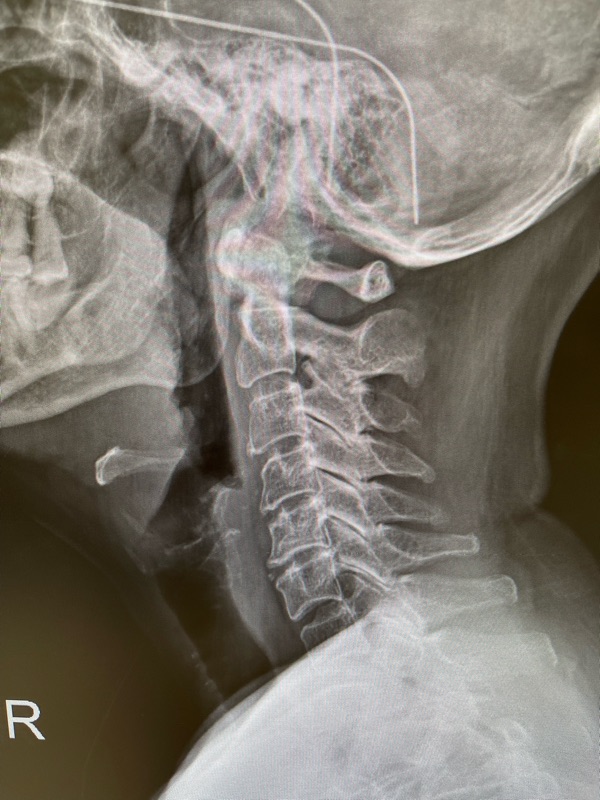

2) X-ray คอ

พบช่องหมอนรองแคบลงที่ C5–C6 (บอกว่าข้อต่อเสื่อมจริง)